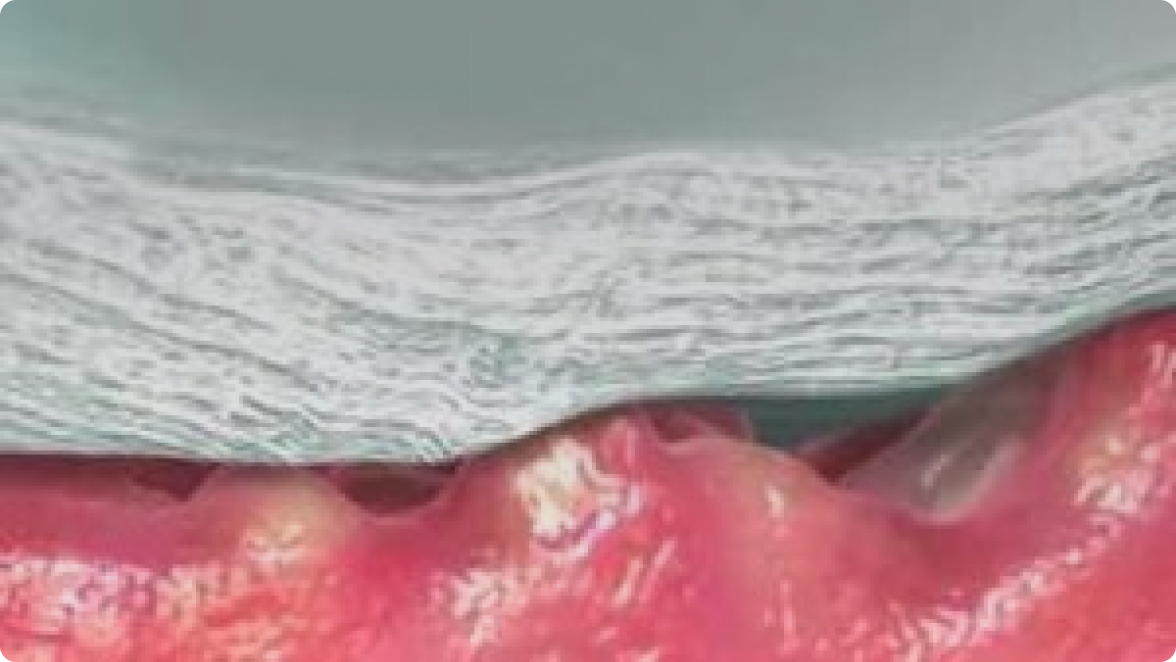

Se microadapta al lecho de la herida*8

Contacto íntimo